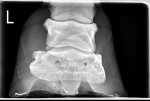

X-rays showed nothing too concerning, thankfully. No sinking, 6degrees rotation on bad foot and 4 on other, but given how sore she is, vet was very relieved and prognosis is good.